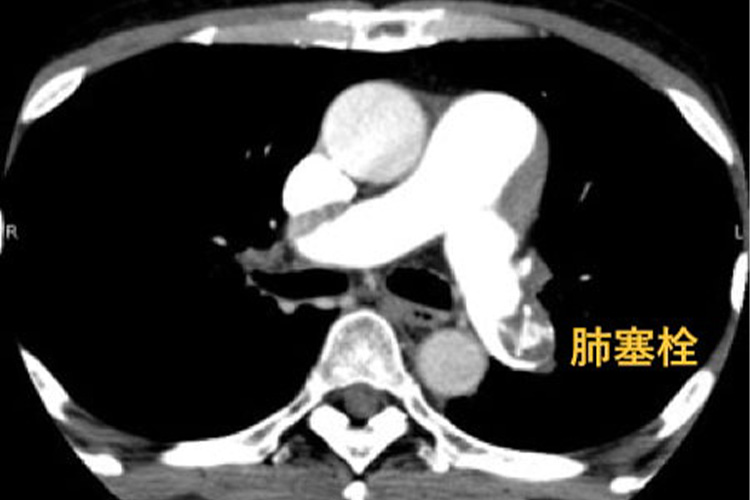

造影CT検査のイメージ

造影剤を静脈注射しCTをとることで、肺血栓塞栓症の有無を診断します。